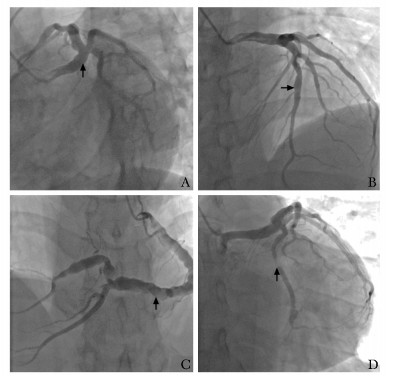

• 摘要: 患者青年男性,早发心肌梗死,合并多囊肾,存在肾病综合征及抗磷脂抗体综合征,冠状动脉造影示多支冠状动脉瘤样扩张伴狭窄闭塞,植入支架后出现支架内反复再狭窄。抗磷脂抗体综合征为反复冠状动脉血栓形成的危险因素,且可累及肾脏并导致肾病综合征,而遗传性多囊肾可有肾病综合征临床表现且可因基因异常合并动脉瘤样病变。遗传因素、免疫因素、代谢因素等均参与其中,经多学科讨论并结合随诊结果,考虑患者为结缔组织病继发抗磷脂抗体综合征、肾病综合征和冠状动脉病变,针对原发病治疗后患者症状及指标均好转。本例患者的诊治拓宽了临床医师对年轻患者冠状动脉疾病背后病因的认识,也体现了多学科诊疗临床思维的重要性。

Abstract: Here we report a case that a young man had early onset myocardial infarction. Coronary angiography showed coronary aneurysm-like dilation and thromboembolism. After stents were implanted, his condition was complicated with repeated stent restenosis. Polycystic kidney, nephrotic syndrome and antiphospholipid antibody syndrome were also present. Antiphospholipid antibody syndrome, a risk factor for recurrent coronary thrombosis, can lead to nephrotic syndrome. Polycystic kidney can be characterized by nephrotic syndrome and may be combined with aneurysmal lesions due to genetic abnormalities. According to the multidisciplinary discussion and follow-up results, the patient was diagnosed as connective tissue diseases and secondary anti-phospholipid antibody syndrome, nephrotic syndrome, and coronary artery lesions. The patient's symptoms improved after treatment for the original disease. The management of this patient broadened our understanding of the etiology of coronary artery disease in young patients and demonstrated the importance of multidisciplinary clinical thinking.